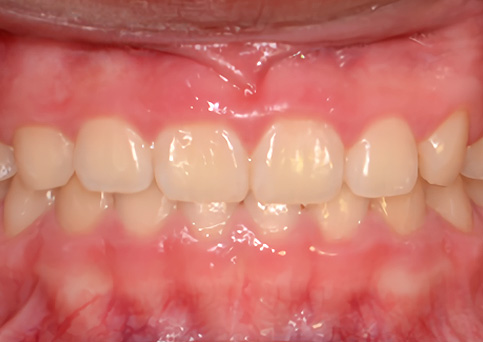

무턱

기능성 교정장치를 통해 작은 아래턱의 자연스러운 성장을 도와주었습니다.

• 주증상

입술돌출, 과개 교합, 무턱

• 치료기간

약 1년

• 부작용

치아표면의 탈회, 치은 부종, 치근흡수 등의 부작용이 있을 수 있습니다.